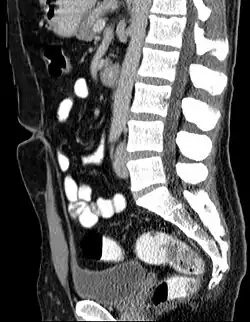

Overblijfsel van de urachus bij een 44 jaar oude man. Links vanaf urineblaas (onder) naar navel (links in het midden). Het ligt in de holte tussen het peritonaeum parietale (buikvlies) en het peritonaeum viscerale (vlies om de ingewanden). -